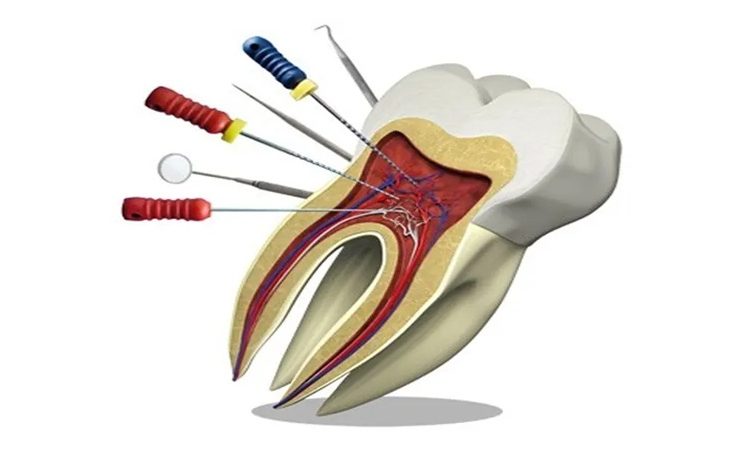

حفظ دندان و جلوگیری از شکستگی پس از انجام درمان ریشه، دندان ممکن است شکننده شود و نیاز به ترمیم مستقیم برای بازگرداندن استحکام و زیبایی دارد. این ترمیمها به عنوان راهی سریع و مؤثر برای حفاظت از دندان درمانشده شناخته میشوند. در این مقاله از سایت دکتر حسین برجیان (بهترین دندانپزشک اصفهان _ بهترین